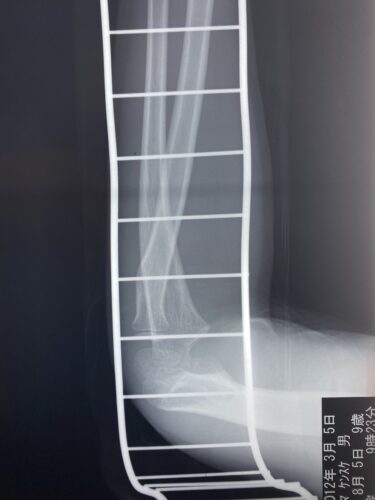

春日部市市民活動センター(前腕骨骨幹部骨折)

第26回整骨研究会「賜恩」研修会開催